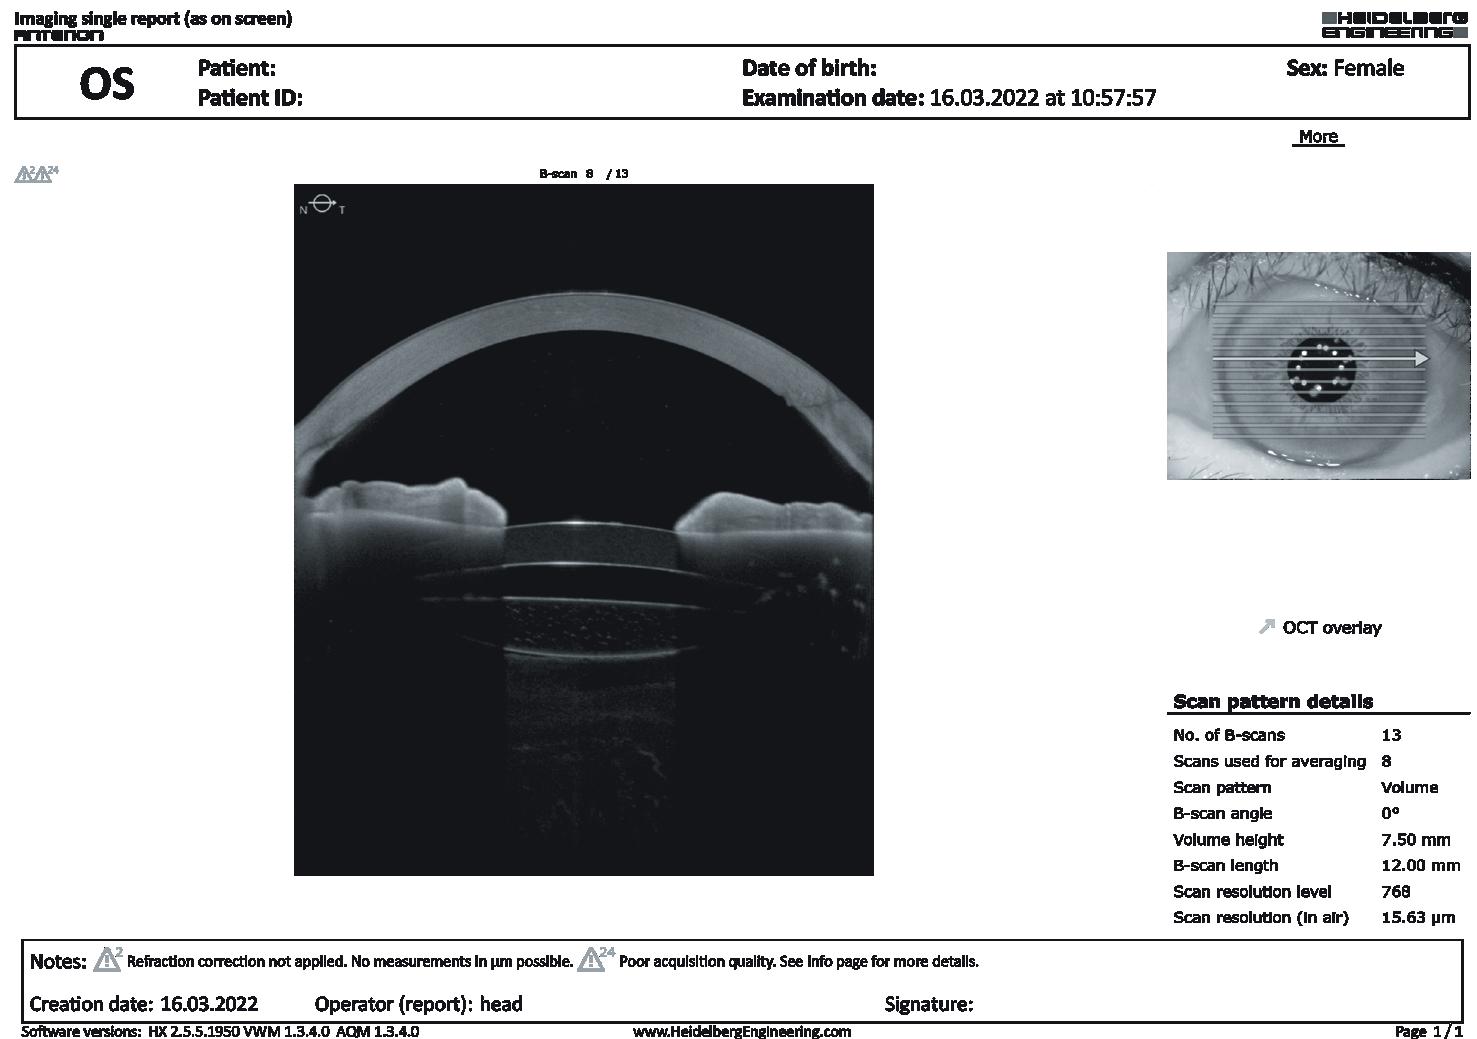

Retinal Considerations for Cataract Surgery

Don’t lose sight of retinal disease when visualising outcomes.

By Dr Soosan Jacob MS, FRCS, DNBFar from the realms of the cataract surgeon but still crucial to planning and outcomes, appropriate knowledge about retinal diseases is important when contemplating cataract surgery. The goal is to provide a good visual outcome without exacerbating underlying retinal disease or creating any new problems with the retina.

EPIRETINAL MEMBRANE (ERM) AND VITREOMACULAR TRACTION

Studies have shown roughly 7–8% risk of CME after cataract surgery in eyes with epiretinal membrane (ERM). Vitreous liquefaction and forward movement of the vitreous are known to increase the risk of CME. Epiretinal membranes are more common in diabetics, and these further increase the risk of CME. In addition, the ERM may progress more quickly after cataract surgery necessitating surgery. The decision to combine phacoemulsification with ERM peeling depends on the visual significance of the ERM. Amsler grid distortion and disruption of the outer retinal anatomy on OCT are indications for combined surgery.

RETINAL TEARS AND RETINAL DEGENERATIONS

Cataract surgery may cause retinal detachment (RD) in the presence of high-risk retinal lesions. Such lesions should therefore be treated prior to surgery. Explain symptoms of retinal detachment and advise the patient to report symptoms immediately.

Pre-existing floaters may become more noticeable after cataract surgery and vitreous liquefaction may induce new floaters. In this case, employ phacovitrectomy or cataract surgery followed by vitrectomy.

RETINAL COMPLICATIONS OF CATARACT SURGERY

Cataract surgery can also induce retinal complications. These range from globe perforation during the peri-ocular block to posterior capsular rent (PCR) with ensuing vitreous loss, nucleus or IOL drop, and/or retained lens fragments. Several factors may increase the risk for CME, vitreous base traction, retinal tears (including giant tears), and retinal detachment. These include chamber fluctuations, PCR or other complications, postoperative inflammation, complex or comorbid eyes, and certain inappropriate surgical manoeuvres. Pseudophakic rhegmatogenous retinal detachment occurs in about 1% of cases, with 50% occurring within the first year of surgery.

Prophylactic topical steroids and NSAIDs are of use in patients at risk for CME. Treatment is also with topical NSAIDs and steroids. For resistant CME, try intravitreal and peri-ocular steroids. Try anti-VEGFs for non-responsive persistent CME. Consider YAG laser vitreolysis, surgical release of vitreous adhesions, and iris capture in select situations.